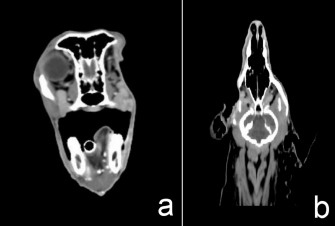

CT for 4 weeks after the surgery demonstrated a heterogeneous mass effect (0.6 × 0.8 cm) in the right caudal maxilla area which extended to part of the right retrobulbar mass with hyper density contrast enhancement (Fig. 4). There was no detection of soft-tissue nodules in the lungs. The radiation treatment plan aimed to control retained mass and micro metastasis.

After radiation

After complete radiation, the dog had normal clinical signs with some hair loss at the radiation site. The CT images showed no detectable recurrent tumor or abnormal contrast enhancement in the right retrobulbar and zygomatic areas. After radiation treatment for 11 months, the CT images showed no detectable recurrent tumor or abnormal contrast enhancement in the right retrobulbar and zygomatic areas (Fig. 5).

Fig. 4. Transverse (a) and dorsal (b) computed tomographic images in the right retrobulbar, maxilla, zygomatic, and temporal areas with mass effect at right caudal maxilla area, extending to part of right retrobulbar mass with hyper density contrast enhancement.

Fig. 5. After 11 months of complete radiation treatment, transverse (a) and dorsal (b) computed tomographic images in the right retrobulbar, caudal maxilla, zygomatic, and temporal areas without mass effect or abnormal contrast enhancement.